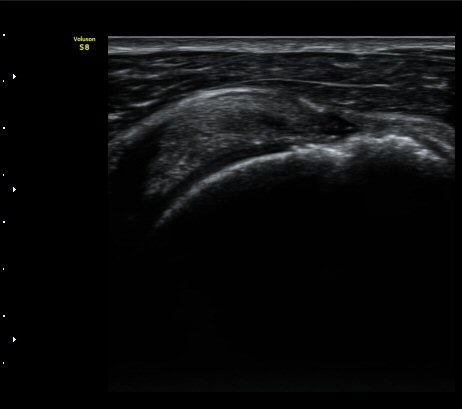

À̵Π¹Ú±Ù°Ç Ⱦ´Ü¸é°Ë»ç¿¡¼­ ƯÀÌ ¼Ò°ßÀ» º¸ÀÌÁö ¾ÊÀ½(»çÁø 1)